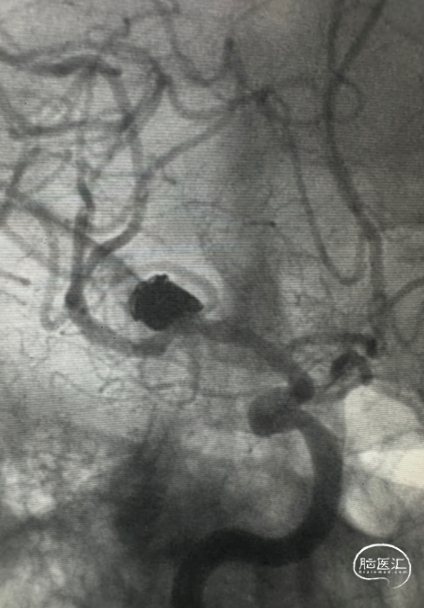

术前影像

右侧M1段分叉部动脉瘤,瘤颈累及M2段上下干支;

动脉瘤大小:8.3mm*8.4mm;